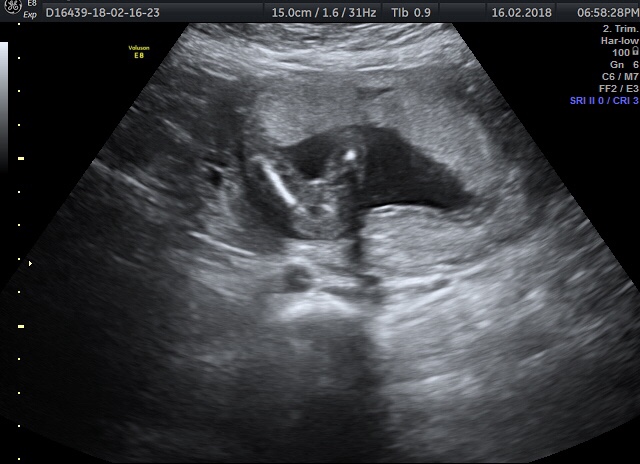

I was told girl again (after being told at 16w) saw lines in the scan but on the pics I was given there are no magic 3 lines 🙄 would you be happy to say girl or wait and try again on another scan?!Attachment 38836Attachment 38837Attachment 38838

I have been told girl at 3 separate scans now and I still can't believe it!!!